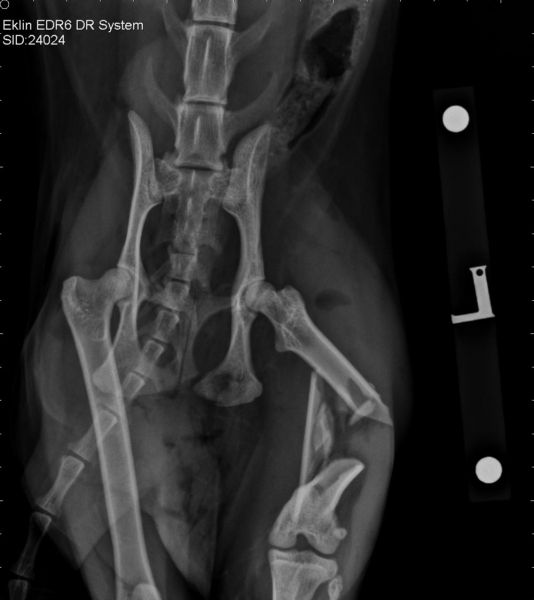

When Lara arrived at the clinic it was clear she had serious issues with one of her back legs with an obvious fracture. Noel rushed the beautiful little cat into the clinic for assessment and once the x-ray pictures appeared on the screen it was clear she had a serious fracture of her femur (thigh bone).

Her femur was in multiple pieces and without surgery to realign and stabilise the fracture her leg would have to be amputated. Noel had to perform tricky reconstructive surgery to rebuild Lara’s shattered leg. Noel inserted a long plate and screws inside Lara’s leg to realign the fracture and hold it in place while it healed.